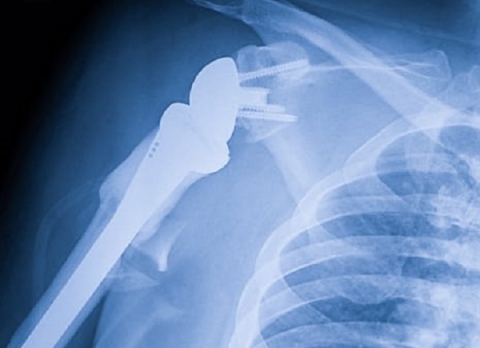

Недавно в Нижнем Новгороде произошел случай, который стал настоящим примером медицинских достижений. Мужчина, получивший тяжелую травму плеча, теперь имеет шанс вернуться к полноценной жизни благодаря установке искусственного сустава.

По информации телеграм-канала «Бокал прессека», операция прошла успешно, и восстановление пациента идет по плану. Сложные травмы плеча могут привести к тяжелым последствиям, включая инвалидность, если не обеспечить должное лечение.

Данная ситуация подчеркивает важность современных медицинских технологий и профессионализма врачей. На сегодняшний день, операции по установке искусственных суставов становятся все более распространенными и доступными для пациентов.

Врачи, осуществлявшие операцию, отметили, что в нашем регионе есть все необходимые условия для проведения подобных вмешательств. Это касается как наличия высококвалифицированных специалистов, так и современного оборудования.